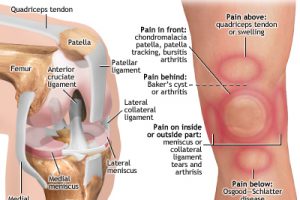

ひざ痛だから膝そのものに着目することも大切なのは否めないのですが、部分だけを見て全体像を見ないことにより、改善できないことはよくあると思います。

ひざ痛の方に多いO脚タイプの方は、カカトが外側に倒れるた状態が普段から普通の状態になってしまうと、その上の足首(足関節)が底屈・内返し、スネの骨(脛骨)が外旋・外倒れ、膝関節が内反・内旋、大腿骨が外転・外旋というふうに上に向かってどんどん連鎖されていきます。